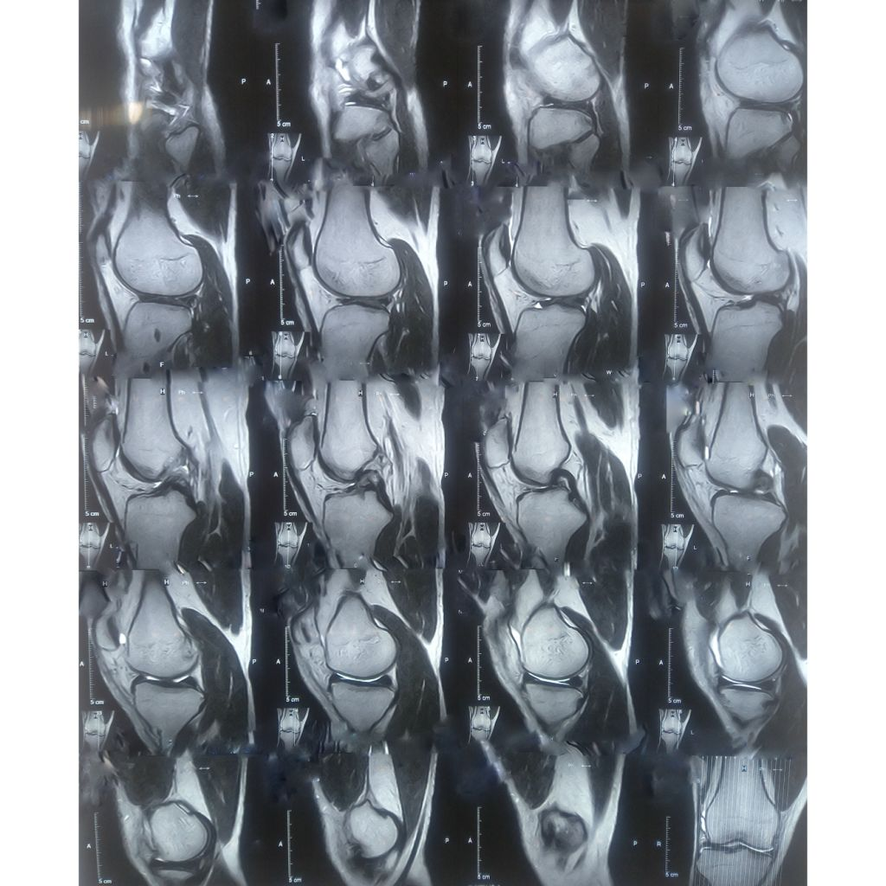

슬개골 탈구는 고양이의 뒷다리에 위치한 무릎뼈인 슬개골이 정상적인 위치에서 벗어나는 상태를 의미합니다. 슬개골 탈구가 발생하면 고양이가 걷는 데 어려움을 겪고, 장기적으로는 관절염 등의 합병증으로 이어질 수 있습니다. 이 문제는 특히 소형 고양이나 특정 품종에서 빈번히 발생하므로, 예방과 관리가 필수적입니다.

슬개골 탈구에서 가장 먼저 나타나는 증상은 걷는 방식의 변화입니다. 고양이가 다리를 절거나 한쪽 다리를 들어 올리는 모습이 자주 관찰되며, 활동 중 불편함을 느끼는 경우가 많습니다. 이러한 초기 증상들은 시간이 지남에 따라 점점 더 심각해질 수 있으며, 계단을 오르내리기 어렵거나 점프를 꺼리는 행동으로 이어질 수 있습니다.

슬개골 탈구의 증상이 나타났다면, 즉시 수의사에게 상담하여 정확한 진단을 받아야 합니다. 이 과정에서 증상의 정도에 따라 물리치료, 약물 치료 또는 수술 등 다양한 대처 방법이 제안될 수 있습니다.

슬개골 탈구는 초기에는 눈에 잘 띄지 않는 증상으로 시작할 수 있습니다. 따라서 정기적인 건강검진은 매우 중요합니다. 전문 수의사는 고양이의 관절 건강을 평가하여 조기 발견 및 치료를 가능하게 합니다. 특히 슬개골 탈구의 위험이 높은 품종의 경우, 이 검사 주기가 더욱 필수적입니다.